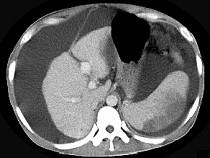

问题 患者男,29岁,乙肝病史10余年,腹胀,有移动性浊音,影像检查如图,最全面的诊断是 ( )

选项 A.肝硬化 B.肝硬化腹水 C.肝硬化腹水、脾梗、胆囊结石 D.大网膜膈下间位及脾梗 E.胆结石及脾梗

答案 C